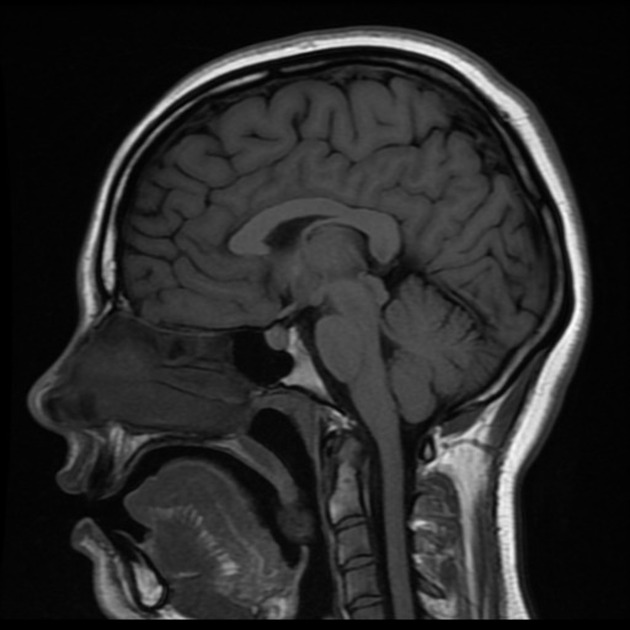

Thank you to MIC Medical Imaging in Edmonton, Alberta. Your excellent imaging & report enabled us to access timely out-of-country cancer diagnosis & treatment for our teenage daughter. You were right, it was cancer!